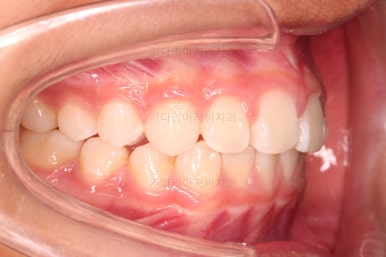

부산소아교정 마무리 사진입니다.

프리올소로 유지과정까지 총 2년 3개월 가량 걸렸고요.

이정도 마무리면 굳이 2차교정까지 안해도 되겠죠?

웃을 때 보이는 느낌도 많이 좋아졌고요.

옆에서 웃는 모습을 보면 윗니도 들어간 모습이 보이죠.

정교한 조절은 안했지만 치열이나 교합/맞물림 등 매우 좋아졌습니다.